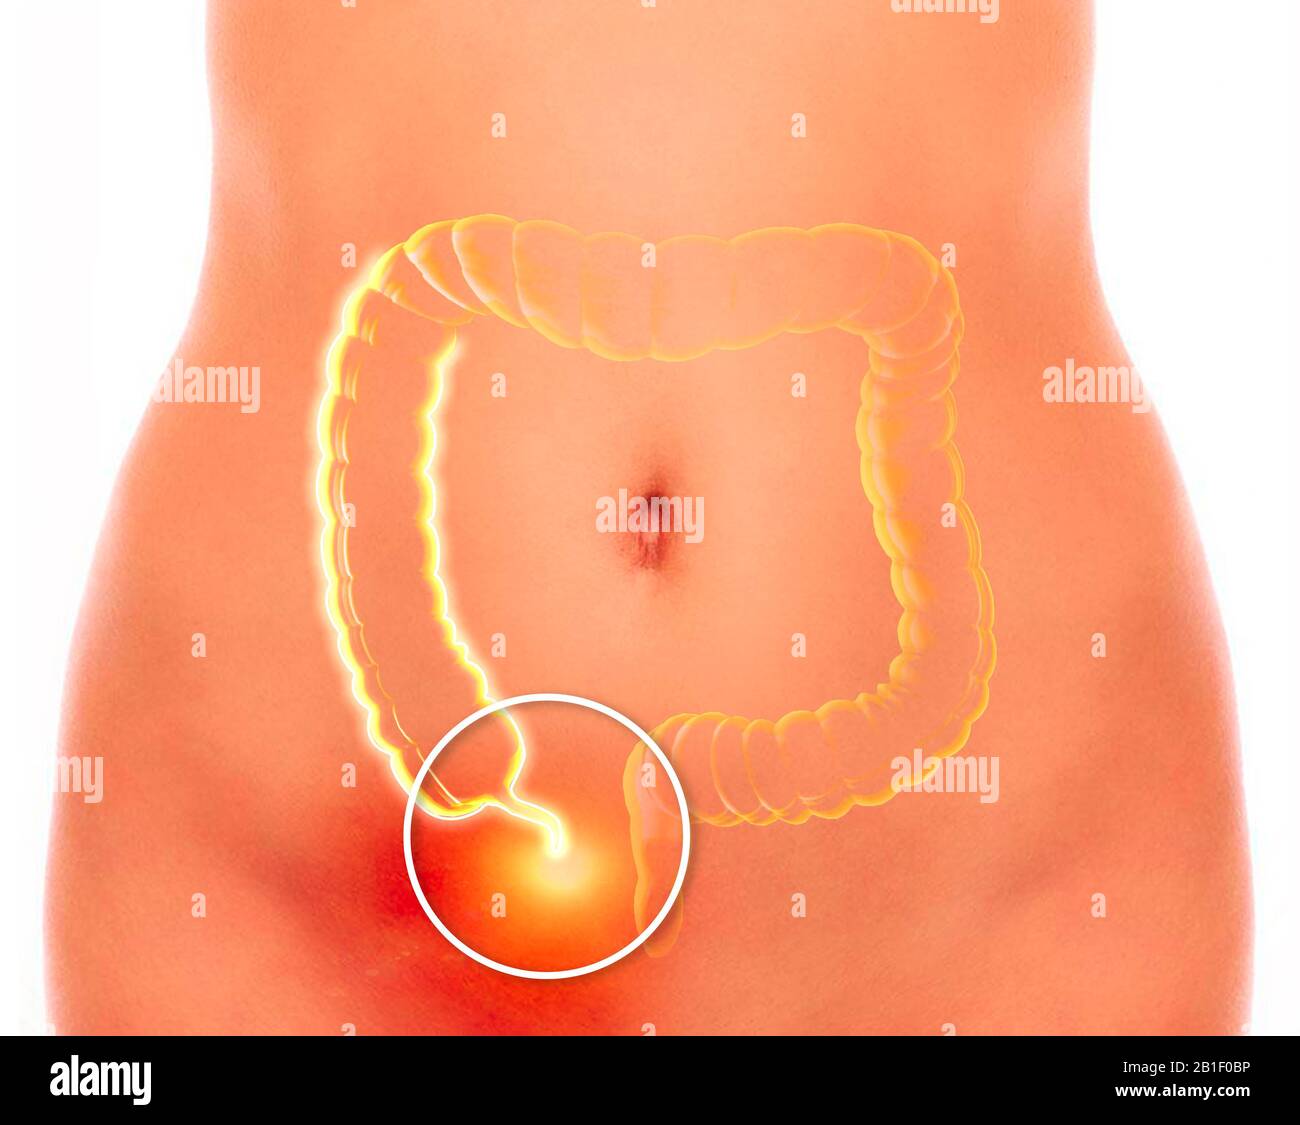

L'annexe est un tube à extrémité aveugle de type doigt connecté au caecum. Le cecum est une structure de type pochette du côlon. rendu tridimensionnel Banque D'Imageshttps://www.alamyimages.fr/image-license-details/?v=1https://www.alamyimages.fr/l-annexe-est-un-tube-a-extremite-aveugle-de-type-doigt-connecte-au-caecum-le-cecum-est-une-structure-de-type-pochette-du-colon-rendu-tridimensionnel-image345151626.html

L'annexe est un tube à extrémité aveugle de type doigt connecté au caecum. Le cecum est une structure de type pochette du côlon. rendu tridimensionnel Banque D'Imageshttps://www.alamyimages.fr/image-license-details/?v=1https://www.alamyimages.fr/l-annexe-est-un-tube-a-extremite-aveugle-de-type-doigt-connecte-au-caecum-le-cecum-est-une-structure-de-type-pochette-du-colon-rendu-tridimensionnel-image345151626.htmlRF2B1F0BP–L'annexe est un tube à extrémité aveugle de type doigt connecté au caecum. Le cecum est une structure de type pochette du côlon. rendu tridimensionnel